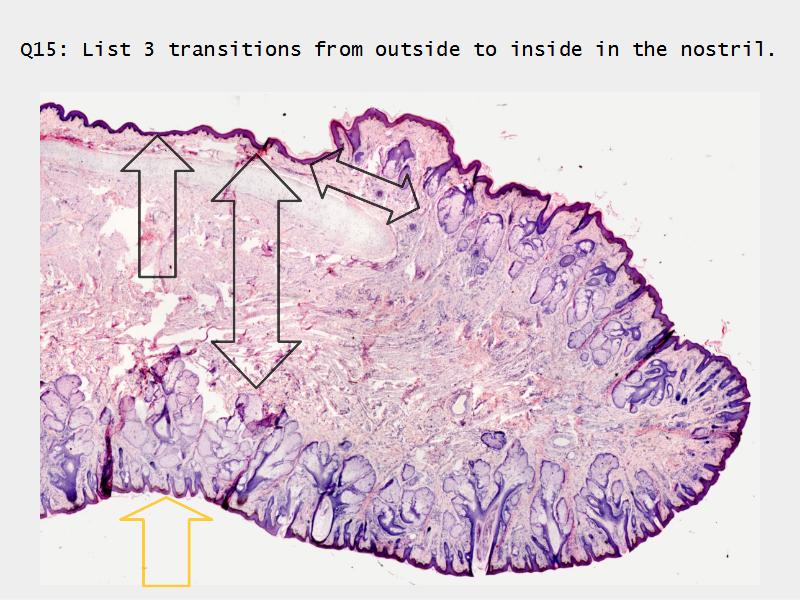

Transitions

- Slide 71: Nostril

Nostril